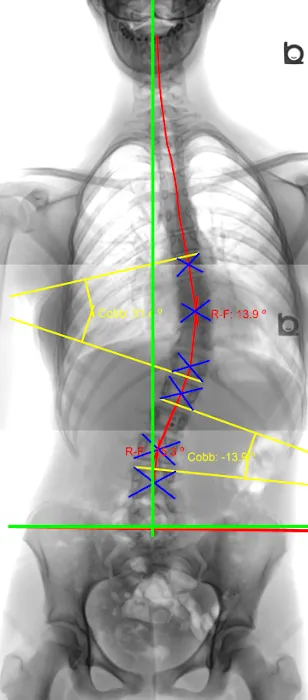

- Scoliosis Management: The center has experience in managing conditions like scoliosis, helping patients who may not have realized they had the condition for most of their lives. Treatment aims to alleviate associated pain and improve spinal health.